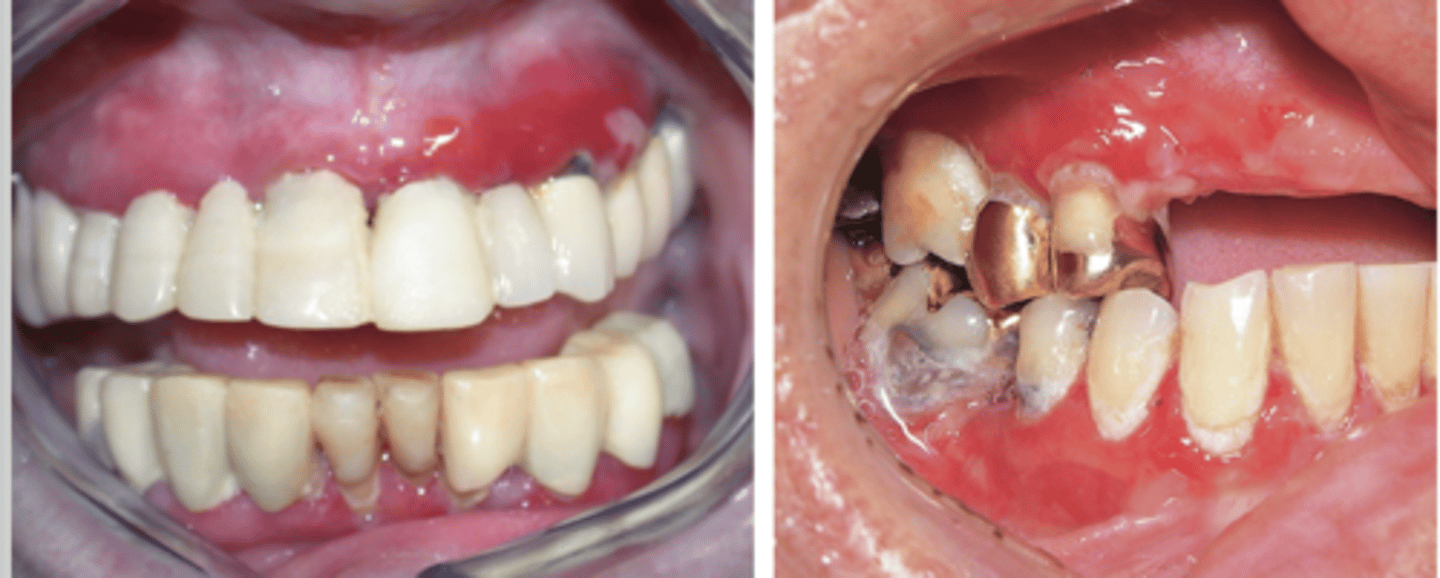

Erosive Lichen Planus

Hint: ulceration with bordered periphery of white radiating striae

Hint: type of lichen planus